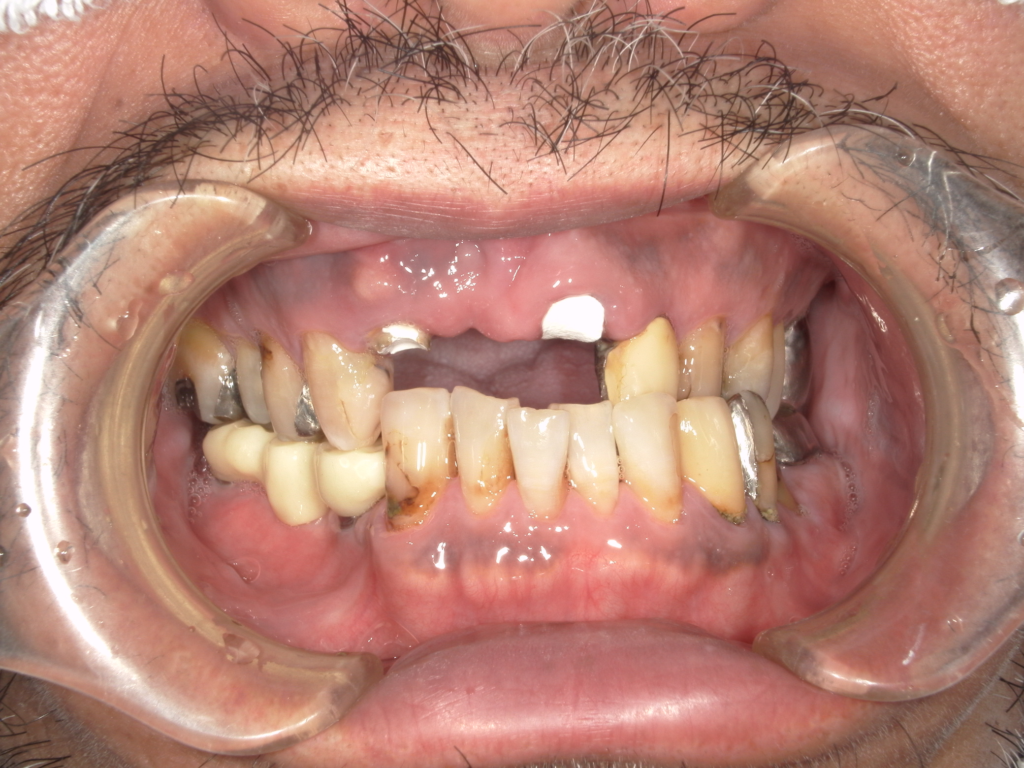

Y様インプラント実例 #44

左の上下の奥歯をインプラントで治療しています。

左下の奥歯は歯を抜くのと同時にインプラントの埋め込みを行っています。

被せものは上下、セラミックスで作っています。

治療前

治療後